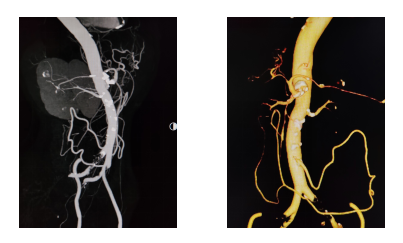

入院后,腹部增强CT检查揭示了病情的严峻性——腹腔干动脉开口处存在严重钙化斑块,造成重度狭窄,血管壁坚硬如石;更为棘手的是,肠系膜上动脉竟异常起源于该狭窄段,并已完全闭塞。两条为肠道供血的关键动脉“命悬一线”。

面对这一高难度挑战,何创业主任带领卫飞鹏医生等团队成员,凭借丰富的复杂钙化病变处理经验,术中精准操控导丝,成功穿透坚硬钙化斑块,顺利开通闭塞的肠系膜上动脉,并采用高压球囊充分扩张后,精准植入支架,成功重建肠道血供“生命线”。